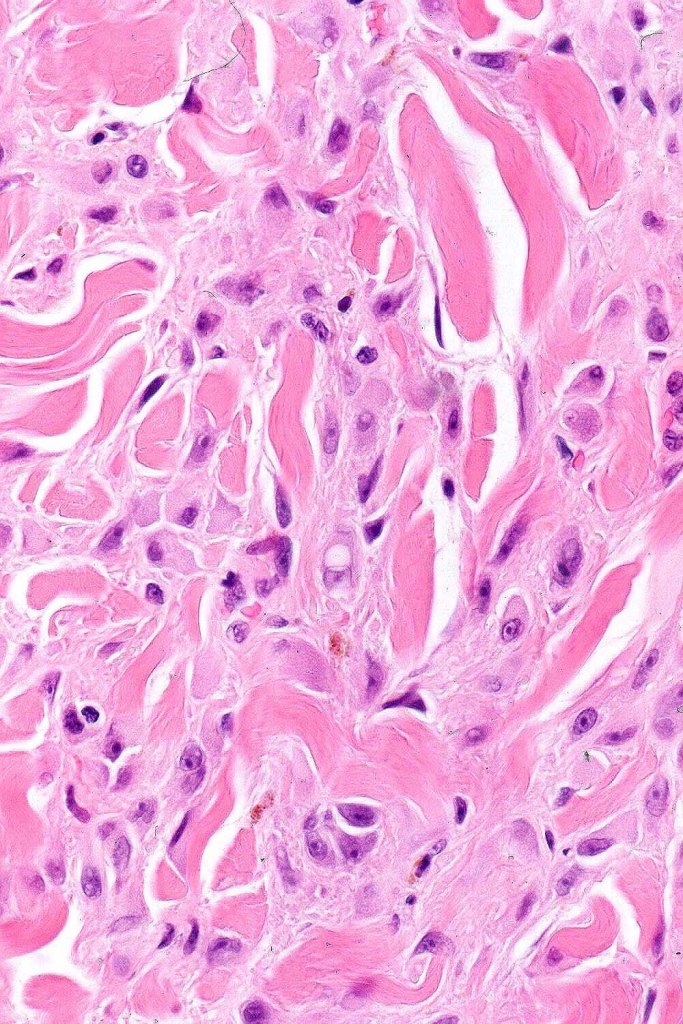

•For the most part, the lesion is composed of somewhat pleomorphic, spindled or epithelioid cells with often abundant eosinophilic cytoplasm & vesicular nuclei with small nucleoli. Melanin is either sparse or absent

•Intranuclear cytoplasmic pseudoinclusions are generally present

•With increasing depth (or age of the lesion), the nevus cells are separated by a dense, sclerotic stroma